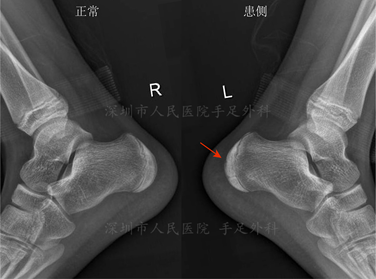

▶X线检查可见跟骨骨骺密度不均匀性增高,骨骺形状不规则,或扁平,或碎裂。但正常儿童也可以出现类似的X线表现,确诊需得结合临床。

图4:跟骨骨骺炎的X线表现,右侧为正常侧,左足跟骨骨骺可见密度增高(箭头)